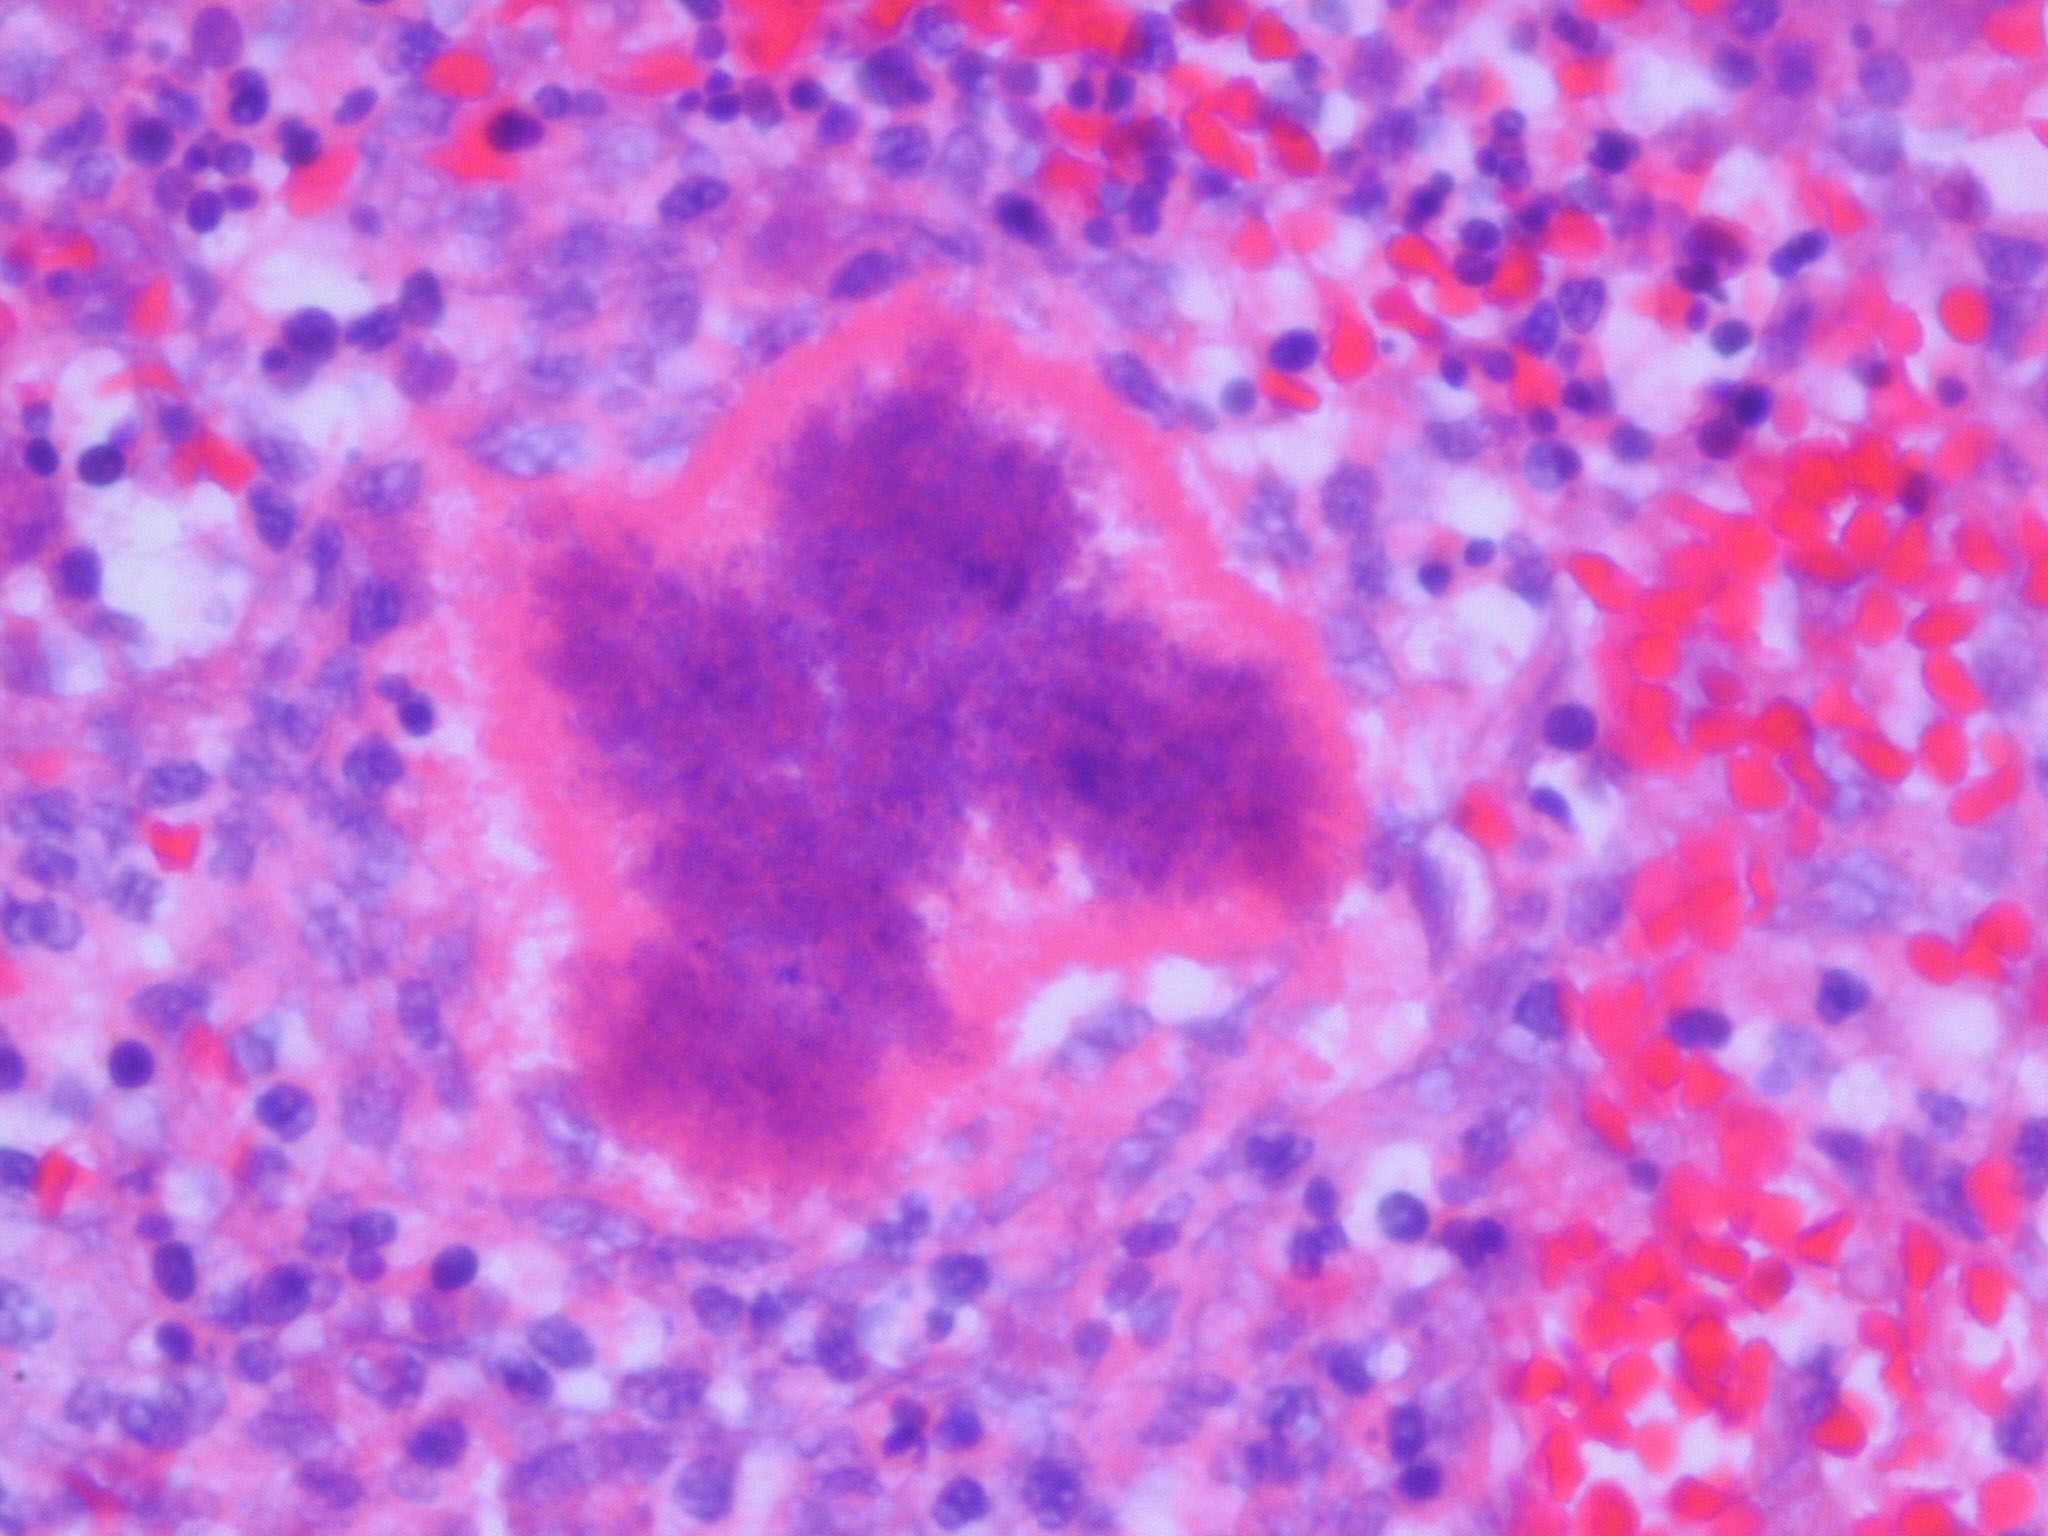

Botryomycosis =الداء العنقودي

OLYMPUS DIGITAL CAMERA